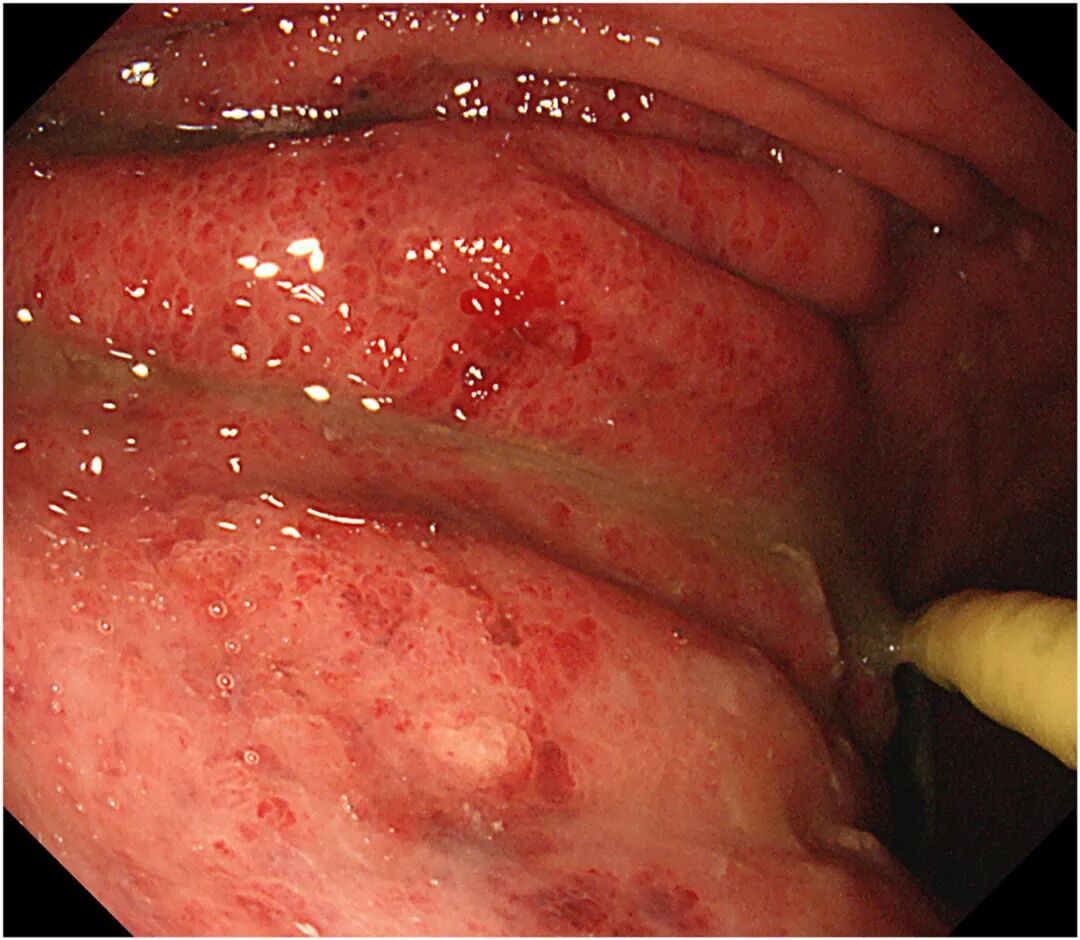

行上消化道内镜检查显示,胃体、胃大弯及前壁黏膜充血水肿(图5)。胃黏膜活检提示轻度慢性浅表性胃炎伴轻度急性活动性(图6),活检培养检出耐碳青霉烯鲍曼不动杆菌。

图5 上消化道内镜显示胃镜显示胃体、胃大弯及前壁显著黏膜充血水肿